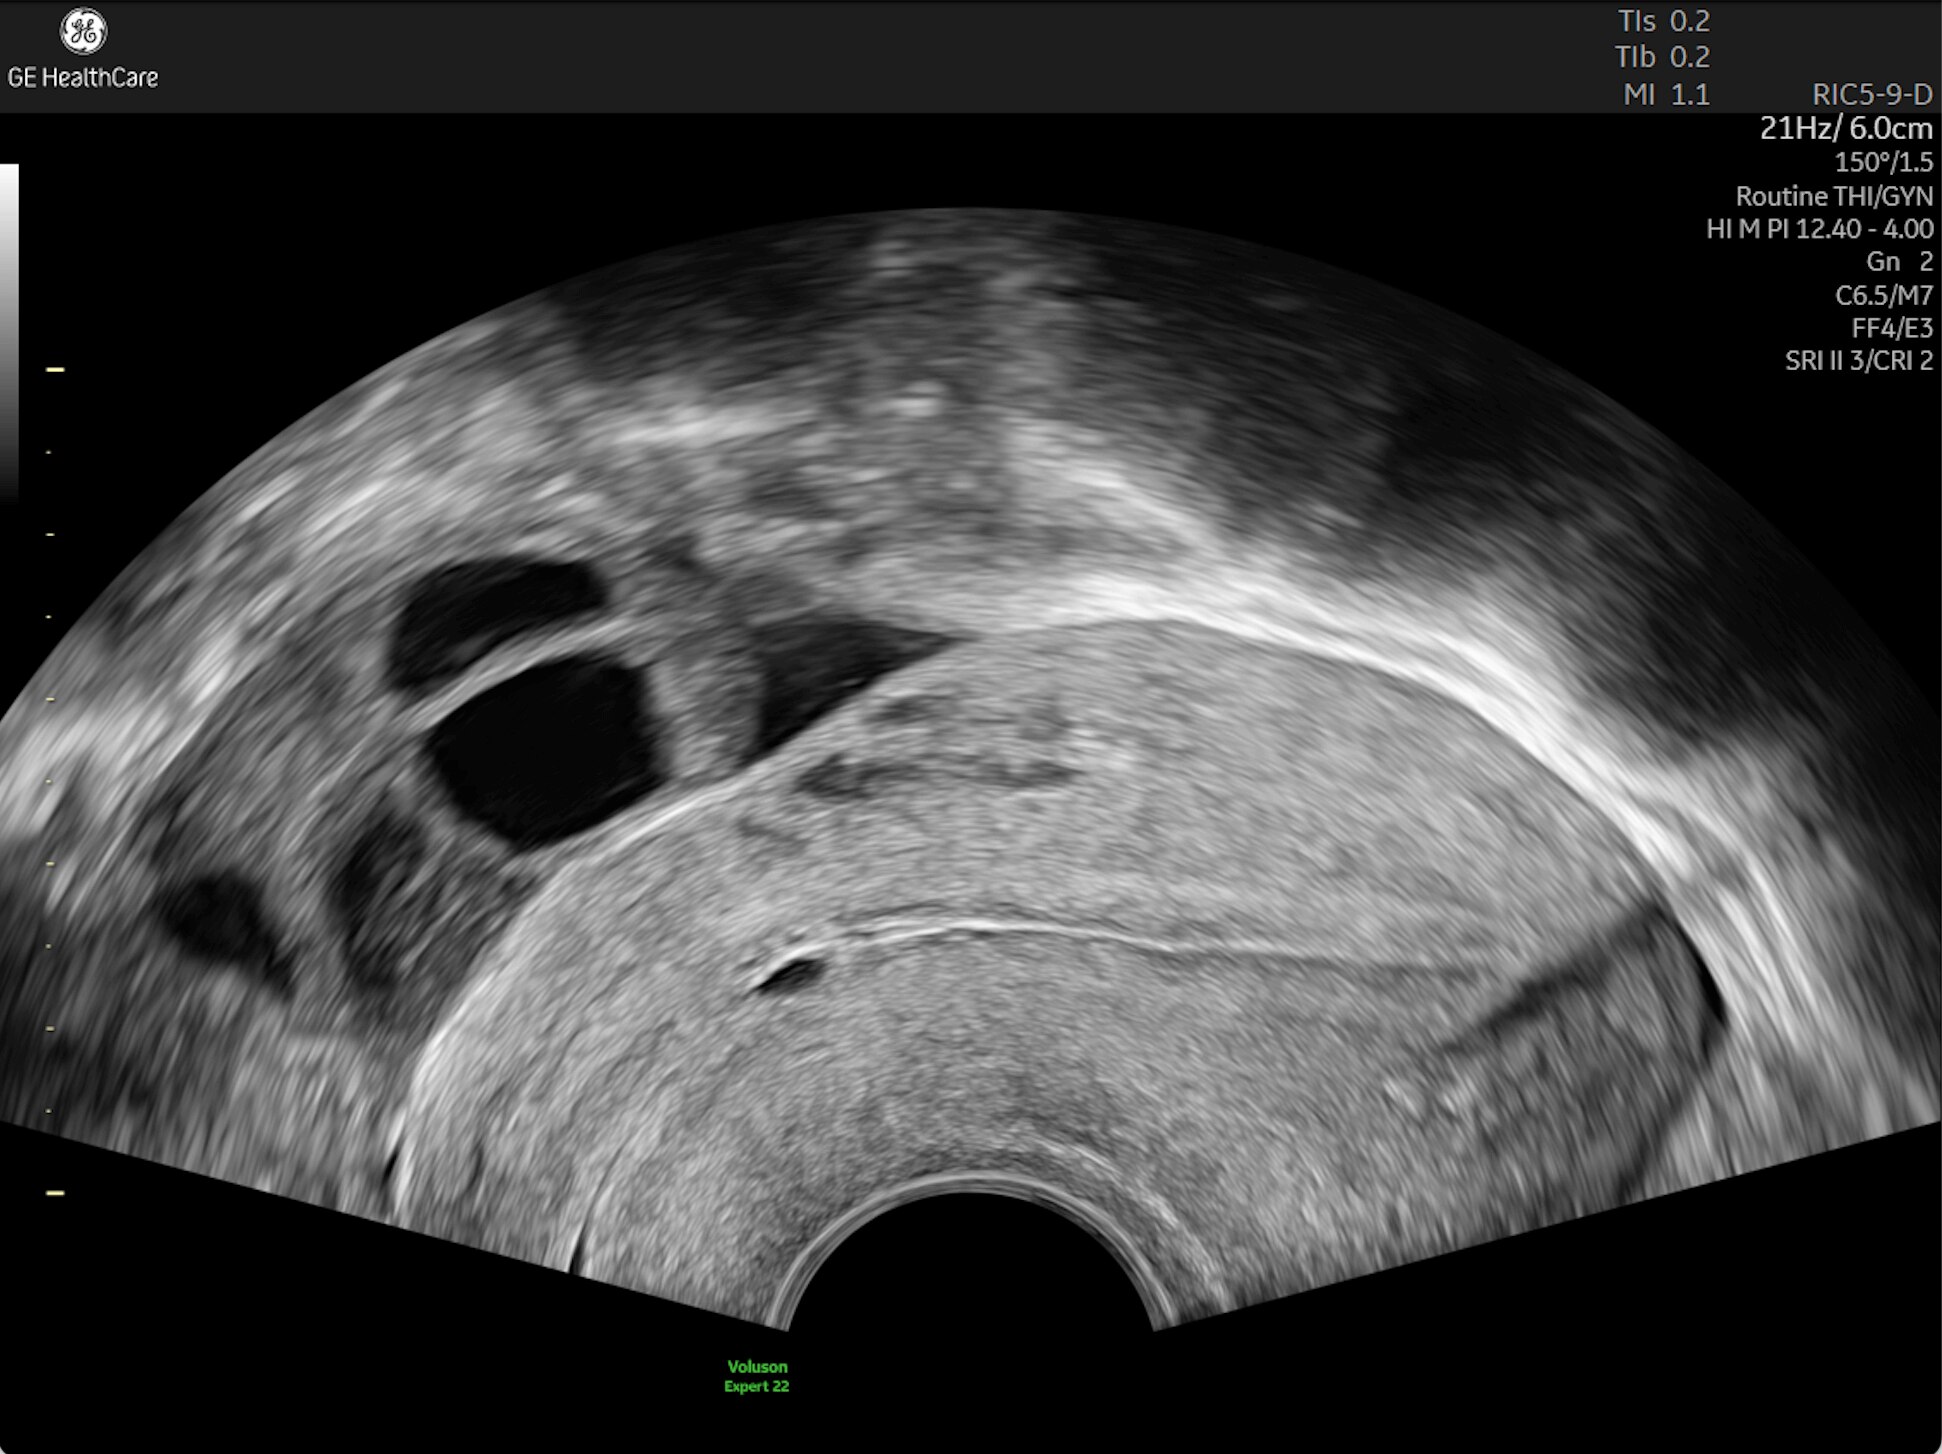

Complex cases come with enough uncertainty. That's why the Voluson Expert 22 is specifically designed for in-depth assessment of complicated anatomy — with pioneering first trimester, fetal cardiac, gynecological, and other pivotal technologies that focus on early detection and intervention.

Identifying fetal cardiac abnormalities earlier means you can intervene sooner, plan for delivery, and potentially improve outcomes. The Voluson Expert 22 provides a full solution of progressive tools, to help distinguish the tiniest structures with stunning clarity to provide patient answers faster.